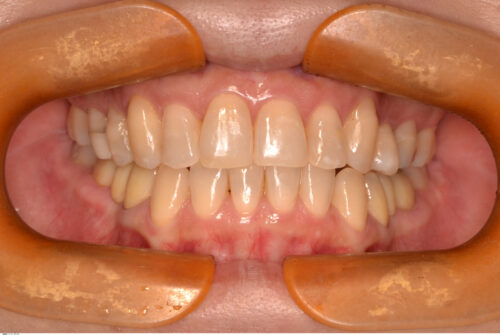

開始から1年で治療を終えました。矯正治療開始直後から、食いしばれなくなるせいか頭痛の改善も認められ、現在も良好に経過しています。

現在術後3年が経過し、後戻りも無くリテーナーの使用も終了しています。

本来であれば欠損部分も矯正によってスペースを無くせばブリッジを入れる必要がなくなるのですが、下顎は骨が硬いため移動に時間がかかります。治療期間を短くすることで患者さんの負担も減るので、成人矯正の場合は補綴処置を組み合わせながら治療計画を立てることも重要だと思います。